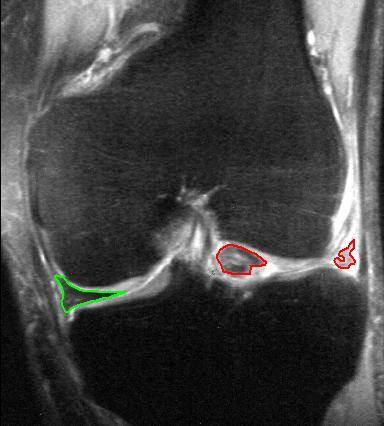

- RMN-ul genunchiului – investigația de elecție pentru menisc

RMN-ul este investigația imagistică cea mai utilă pentru confirmarea unei rupturi de menisc. Acesta permite evaluarea detaliată a meniscului și a altor structuri ale genunchiului.